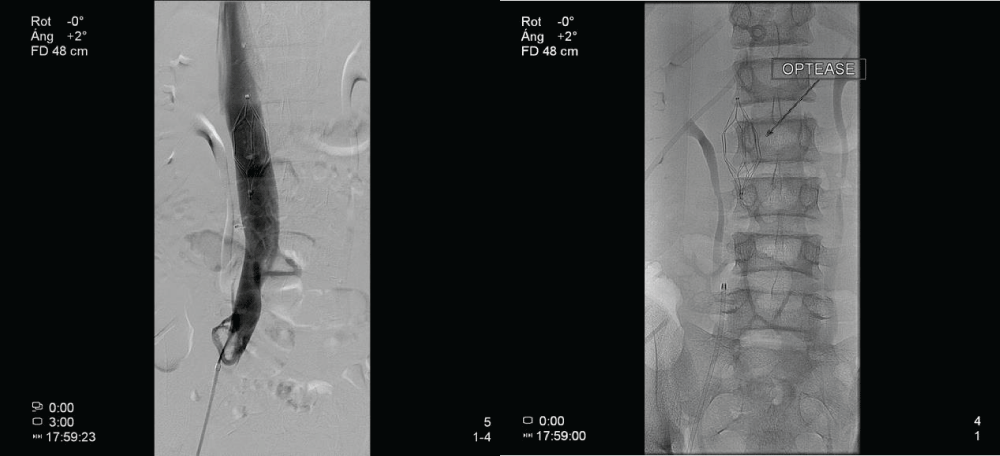

Figure 2:

Image showing placement and location of the vena cava filter in an infrarenal location.